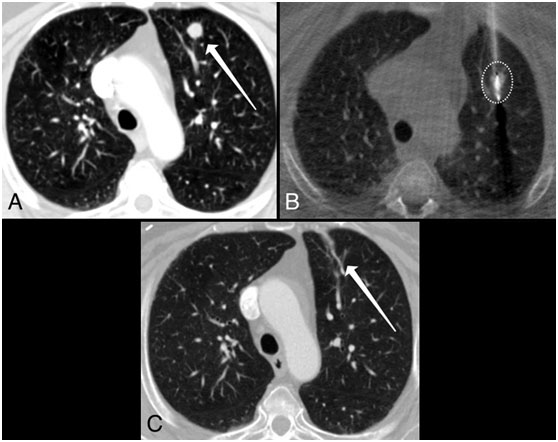

圖示:微波消融治療肺轉(zhuǎn)移。一名74歲轉(zhuǎn)移性子宮內(nèi)膜癌患者的胸部CT圖像顯示,在治療前,肺左上葉有一個(gè)11毫米的肺結(jié)節(jié)(圖A)。治療期間獲得的圖像(圖B)顯示一個(gè)位于肺轉(zhuǎn)移灶內(nèi)的消融探針;白色圓圈表示處理區(qū)域。消融后6個(gè)月(圖C),只留下一個(gè)小疤痕。

圖片來(lái)源:麻省總醫(yī)院官網(wǎng)